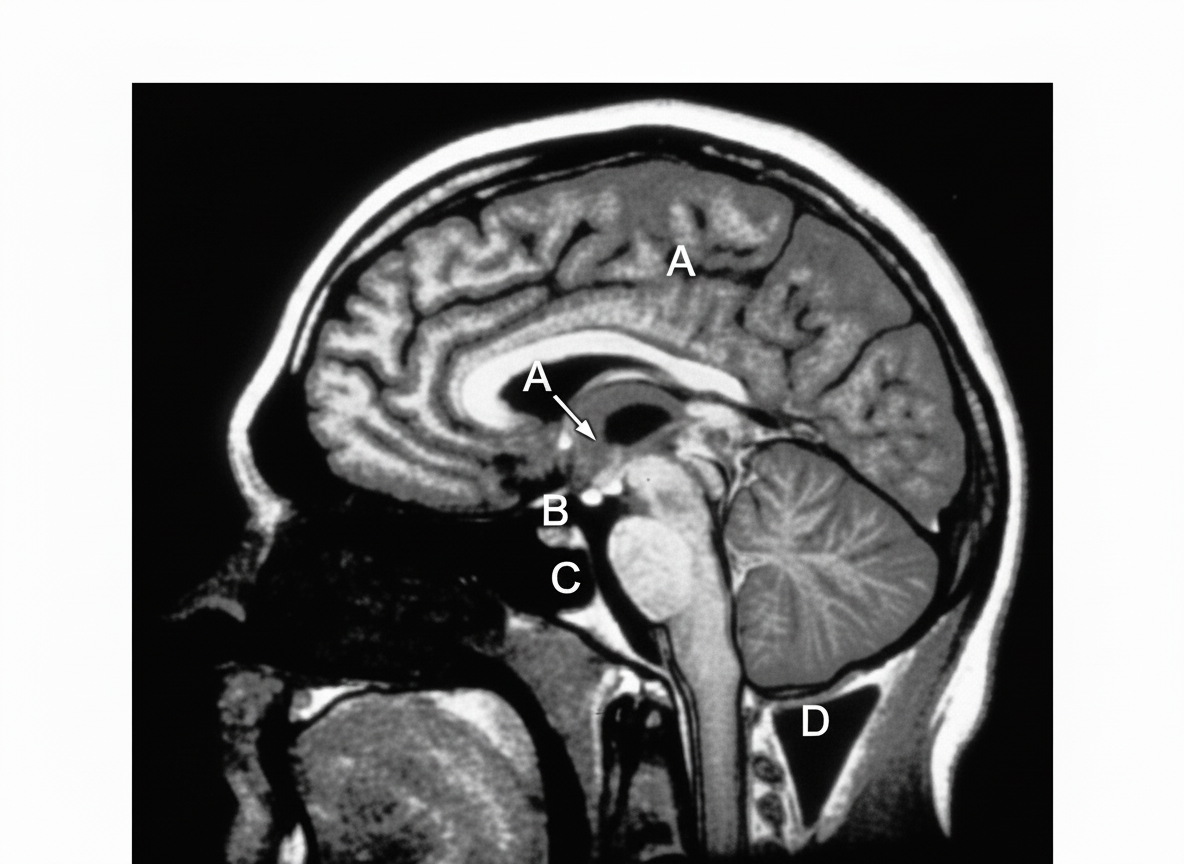

In the provided MRI scan showing a sagittal section through the head and neck, a tumor originating from which numbered structure can be surgically accessed via a transsphenoidal approach, passing through the nasal septum and the body of the sphenoid bone?

Explanation: ***Structure A*** - Structure A represents the **pituitary gland** located in the **sella turcica** of the sphenoid bone, making it directly accessible via the transsphenoidal approach. - This surgical route passes through the **nasal cavity**, **nasal septum**, and **sphenoid sinus** to reach the pituitary fossa, commonly used for **pituitary adenoma** resection. *Structure B* - Structure B likely represents the **brainstem** or **cerebellum**, which are located in the **posterior fossa** and cannot be accessed through the sphenoid bone. - These structures require **posterior craniotomy** or **suboccipital approach** for surgical access, not transsphenoidal. *Structure C* - Structure C appears to be in the **cerebral cortex** or **frontal lobe** region, which is located above the sphenoid bone level. - Access to these structures requires **craniotomy** through the skull vault, not through the nasal cavity and sphenoid bone. *Structure D* - Structure D seems to represent structures in the **cervical spine** or **upper neck** region, which are below the sphenoid bone. - These structures are accessed via **anterior cervical** or **posterior cervical approaches**, not through the transsphenoidal route.